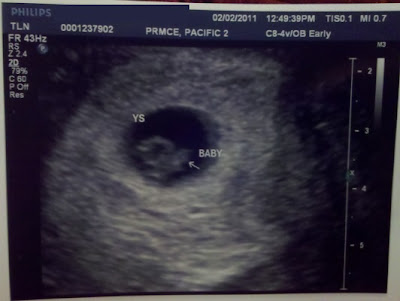

We checked the heartbeat via ultrasound to confirm that baby is still viable. I couldn't see the monitor but she said everything was good.